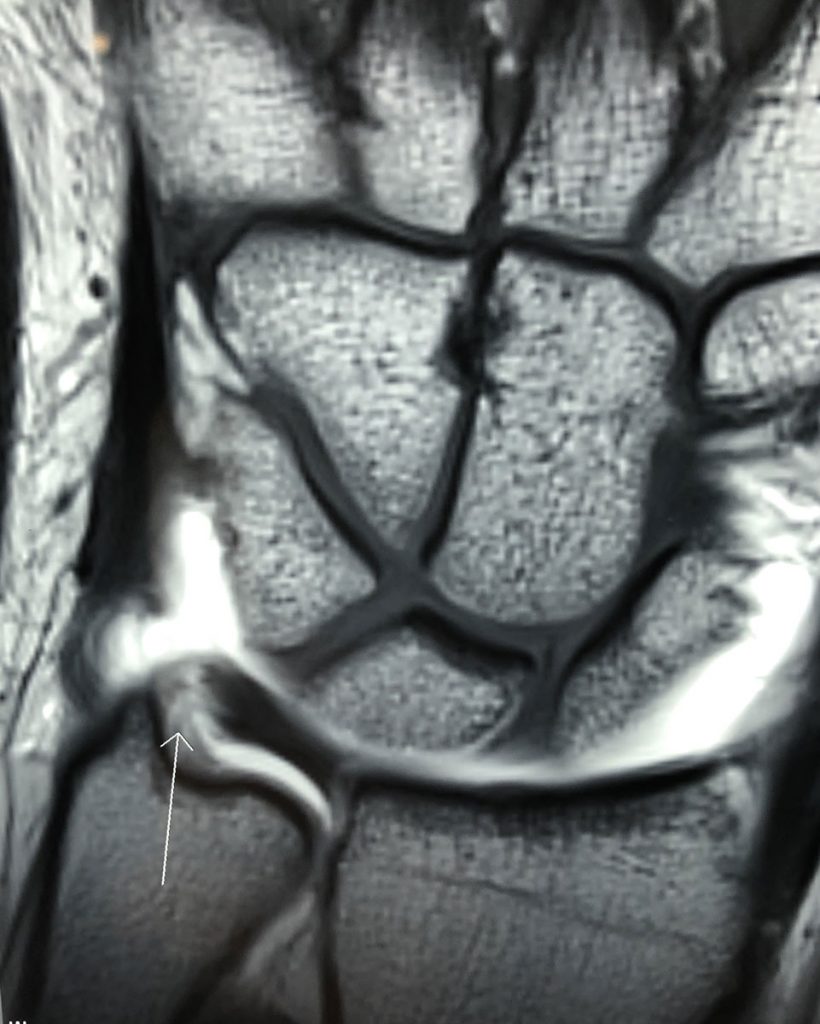

– Lesiones del Complejo Fibrocartílago Triangular (Figura 3). (ver apartado de Lesión del Complejo Fibrocartílago Triangular).

Figura 3 - Lesión del Fibrocartílago Triangular.